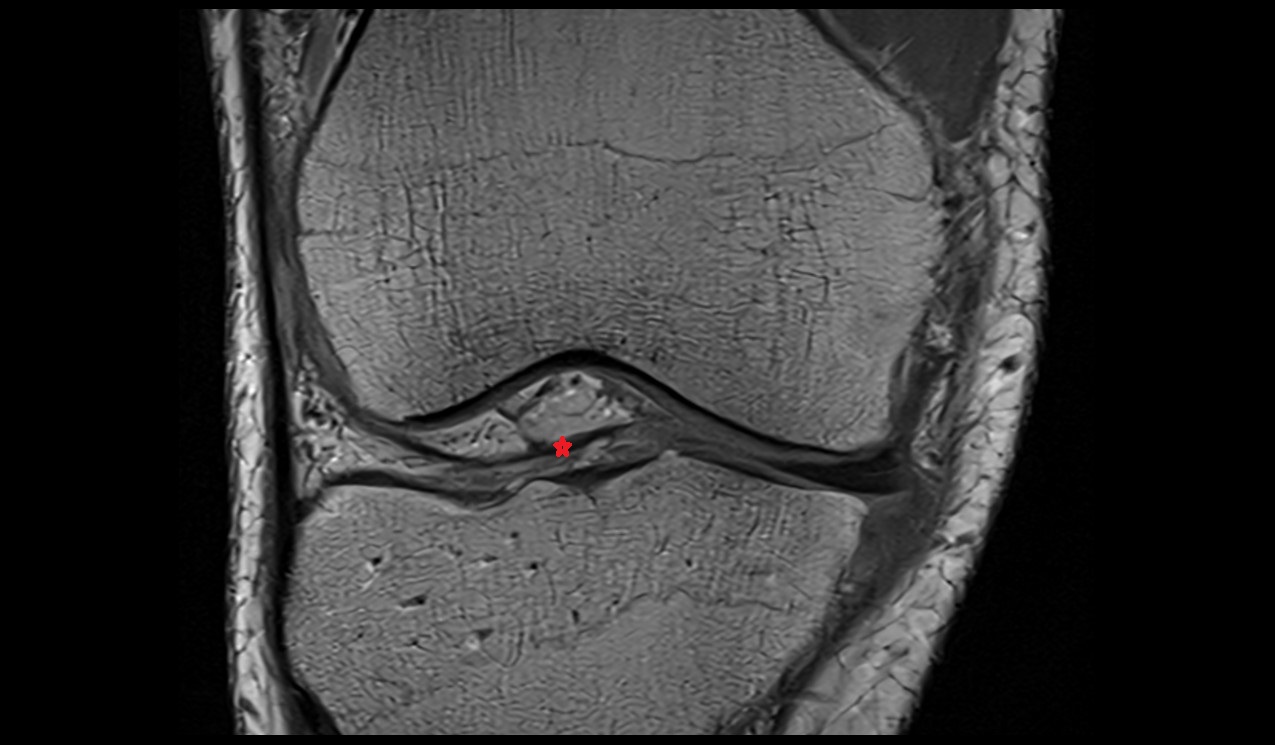

- Medial meniscus

- Lateral meniscus

- Anterior horn of medial meniscus

- Posterior horn of medial meniscus

- Body of medial meniscus

- Anterior root of medial meniscus

- Posterior root of medial meniscus

- Anterior horn of lateral meniscus

- Posterior horn of lateral meniscus

- Body of lateral meniscus

- Anterior root of lateral meniscus

- Posterior root of lateral meniscus

- Knee Joint